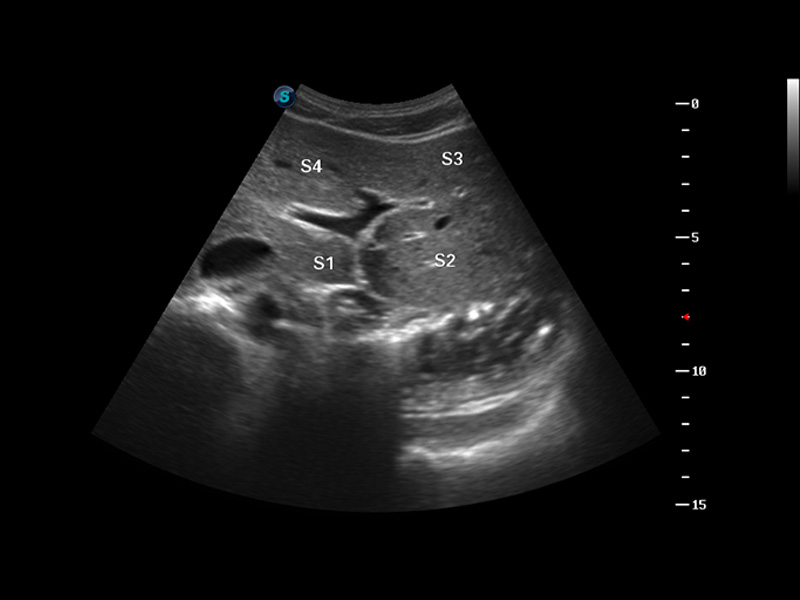

谐波成像

实时宽景成像

空间复合成像